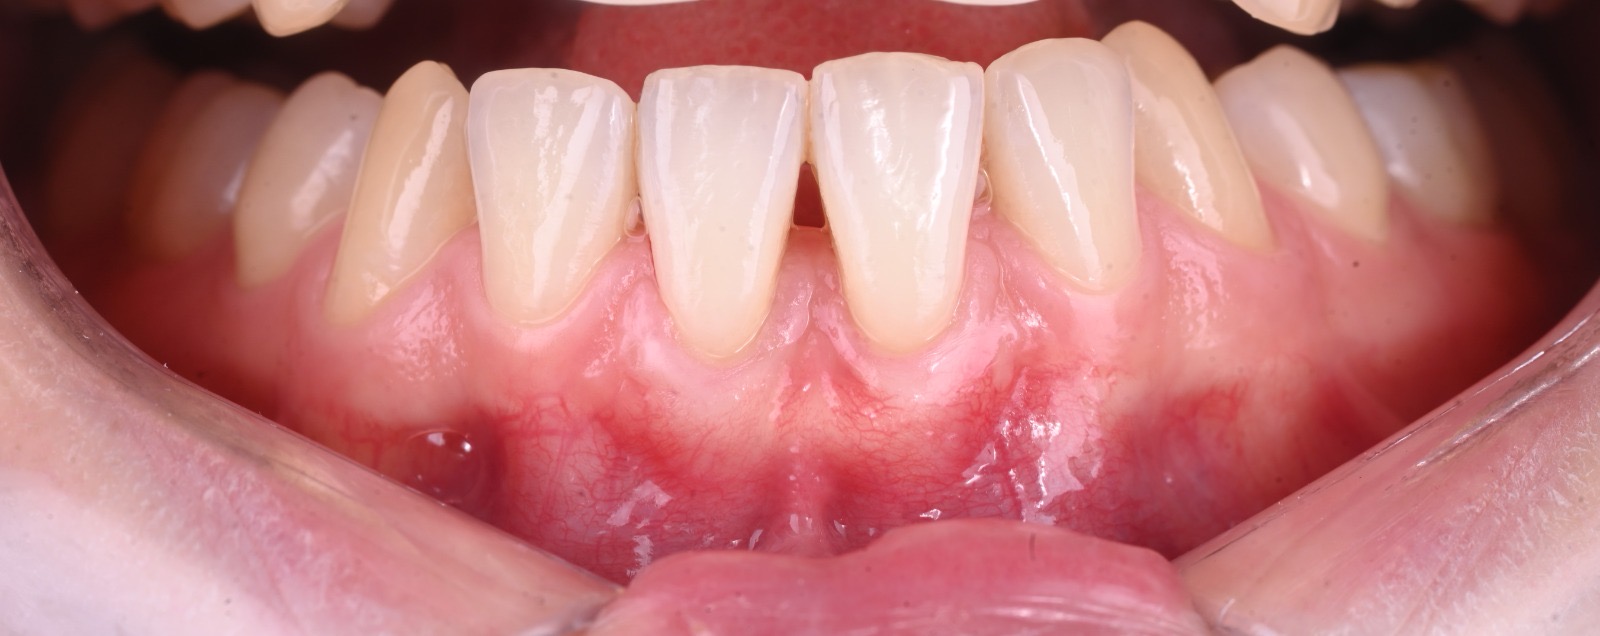

La récession gingivale correspond à un retrait progressif de la gencive qui expose la racine de la dent. Cela peut provoquer :

Une sensibilité accrue au chaud et au froid.

Une gêne esthétique (dents plus longues).

Un risque de caries radiculaires ou de perte d’attache.

Une fragilité osseuse à long terme.